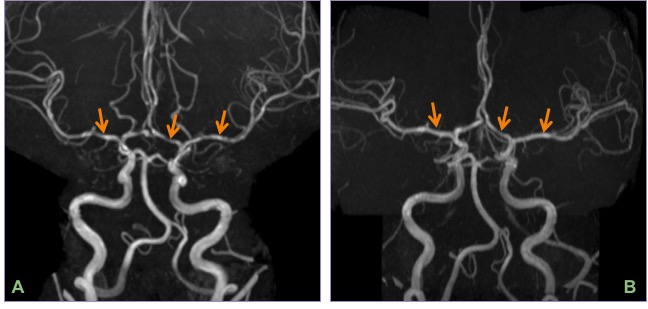

Coronal MIP CT angiogram (A) and right carotid injection DSA (B) showing bilateral severe ICA & MCA narrowing with puff of smoke appearance. Oblique MIP CT angiogram of the neck showing champagne-bottle neck sign seen in advanced cases of Moyamoya disease.

The classic puff-of-smoke appearance of lenticulostriate & thalamostriate collaterals is seen on DSA. Equivalent collateral vessels may be seen on CTA/MRI.

Presence of Champagne bottle neck sign of ICA in the neck suggests a more severe disease and worse prognosis. Please read the AJNR article below for more details.